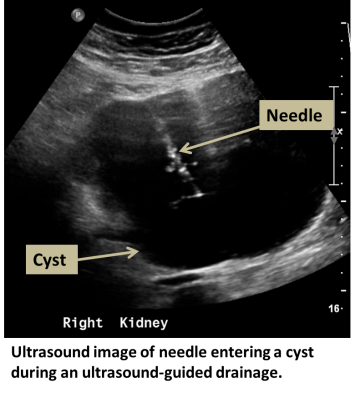

An interventional radiologist or abdominal radiologist uses CT or ultrasound to guide a needle or small drain into one or more cysts. The fluid is then removed by vacuum suction. If cysts are recurrent, sclerosis can be performed by instilling a chemical which damages the cyst wall, reducing its chance of recurrence.